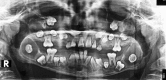

Fibromyxoma of the jaw is a rare benign mesenchymal odontogenic tumor with locally aggressive behavior. In the present report, a 13-year-old female patient presented to our university hospital with delayed eruption of some of her teeth. A panoramic radiograph taken at the initial examination revealed four pericoronal radiolucencies related to the four third molars. Thereafter, a magnetic resonance imaging (MRI) examination was performed. After the surgical removal of these molars, the microscopic examination diagnosed the four lesions as fibromyxomas. Here, we have discussed the clinical, panoramic radiography, MRI, and histopathological findings of the case.